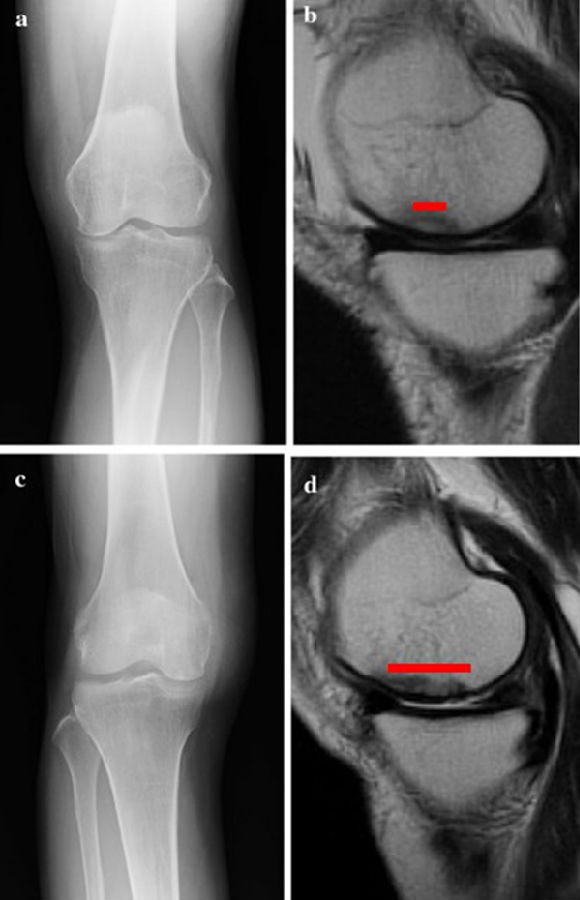

早期(3月内)内侧半月板相对挤压百分比≥33%,是SONK发病1年后预后不良的预测指标,MRI检查没有局灶性轮廓塌陷和髁深处没有低信号线(隔离带),预后好,股胫角>180°(下肢力线内翻>6°)和MRI上深度>20mm 预示SONK患者症状发作后1年预后不良。

内侧半月板挤压(MME)以绝对值和挤压相对百分比 (RPE) 的形式呈现,其定义为挤压半月板宽度与整个半月板宽度相比的百分比

a.患者,59岁女性,AP侧位片显示SONKⅠ期,FTA<180°;b.MRI T2显示病变深度<20mm,患者出现症状1年后保守治疗;c.75岁女性,X线显示SONKⅠ期,FTA>180°;d. MRI T2显示病变深度>20mm,患者于症状出现后11周行手术治疗

影响保守治疗效果的因素